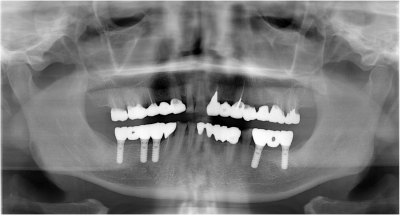

そして、治療技術の向上としては、以前は失った歯の代わりとして義歯(入れ歯)しかできなかったことが、インプラント(人工歯根)を応用することによって、失った機能や見た目を回復し、自分の歯のように快適に食事をすることができるようになりました。

下の歯のインプラント治療終了後

上の歯の治療に入った時のレントゲン写真